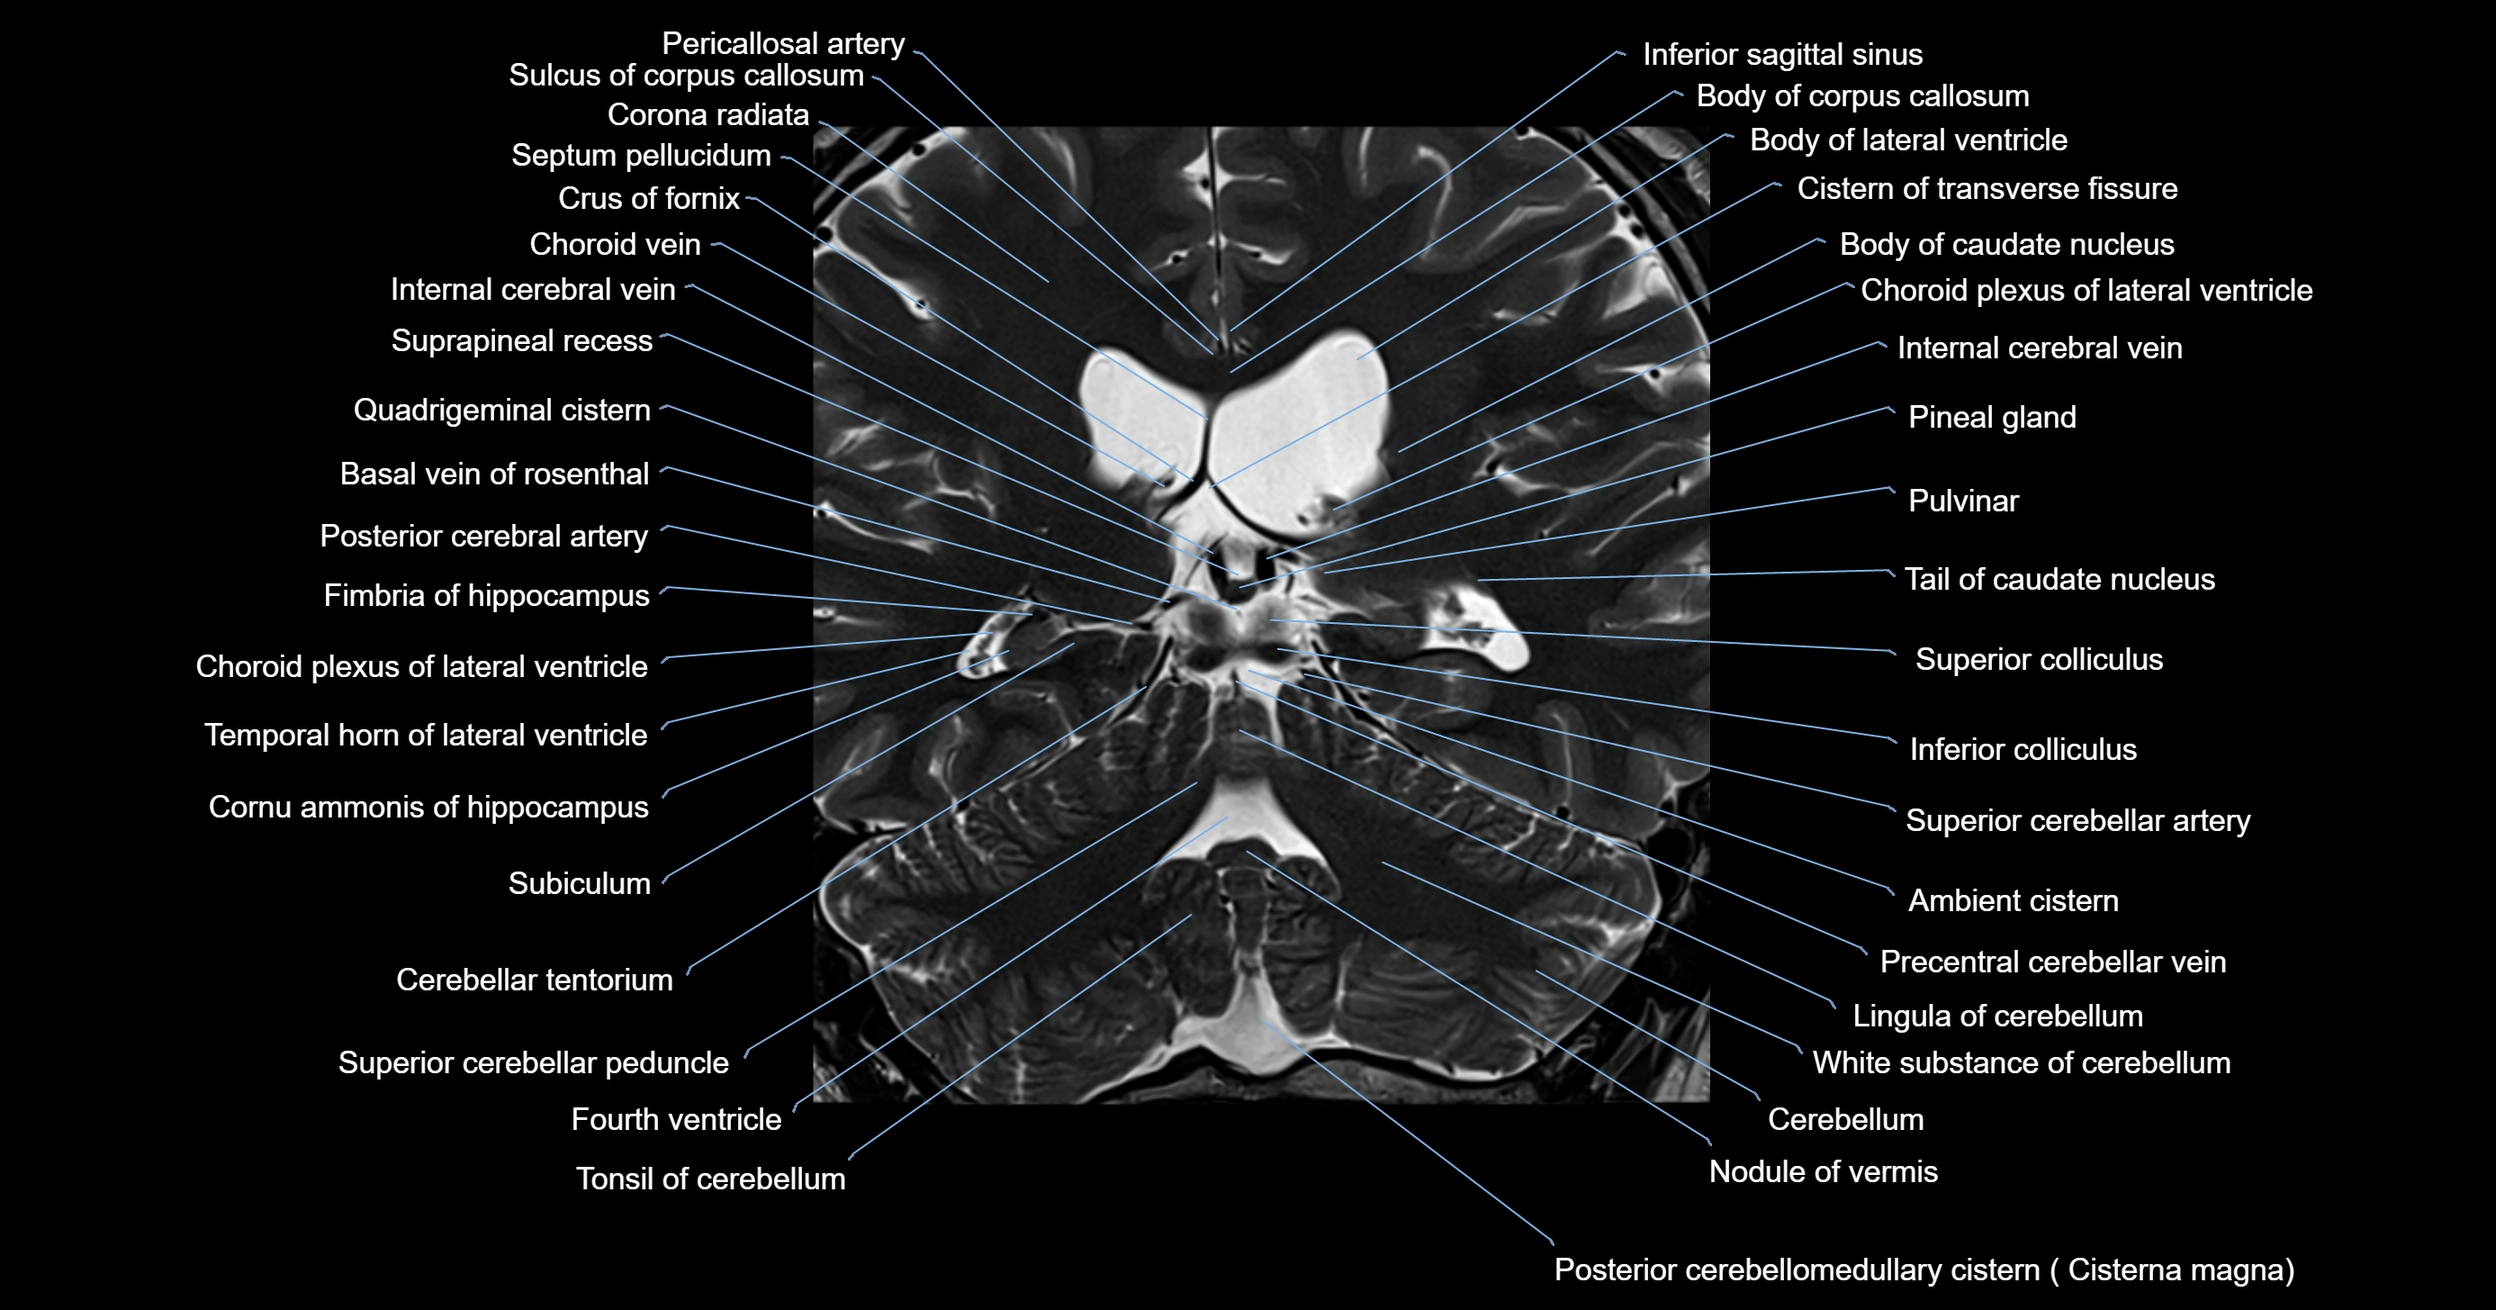

- Ambient cistern

- Basal vein of rosenthal

- Cerebellum

- Cisterna magna

- Fourth ventricle

- Inferior colliculus

- Lingula of cerebellum

- Nodule of vermis

- Posterior cerebellomedullary cistern (cisterna magna)

- Precentral cerebellar vein

- Superior cerebellar artery

- Superior cerebellar peduncle

- Superior colliculus

- Tonsil of cerebellum